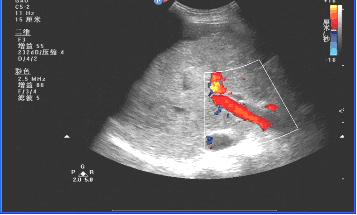

三、慢性肝炎肝硬化时的超声影像:

肝缩小,被膜不光滑,肝回声结节样增粗,门静脉扩张,腹水。